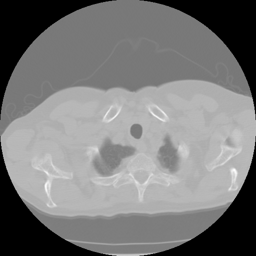

Limited angle CT reconstruction is a very challenging ill-posed issue and of great interest in several clinical applications, such as digital breast tomosynthesis [1], dental tomography [2], short exposure time [3], etc. In a limited-angle CT scan, the projection data can be obtained in less than 180superscript180180^{\circ} angular range, and the data insufficiency degrades reconstruction quality with streaking artifacts(fig 1 (a)(b)).

Figure 1: Qualitative illustration of the task: (a) given a limited-angle sinogram; (b) automatic inpainting result using our sinogram inpainting network (SIN); (c) ground truth sinogram; (d) reconstruction result of state-of-art iterative SART method with TV normalization; (e) our method output; (f) ground truth image